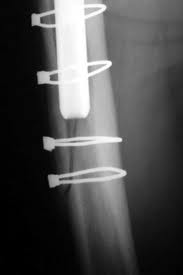

In the doctor reports from the operation states that the devise holding the femur head just fell out, the prosthesis had already grown-in bone (my doctor said that was not to happen) it took the new doctor 5.5 hours remove the first device, during the surgery the doctor tried everything to remove the prosthesis, my femur was fractured, they cut the femur in half to hammer out the device.

Once it was removed they put bands around my femur in 4 or 5 places to hold the bone together.